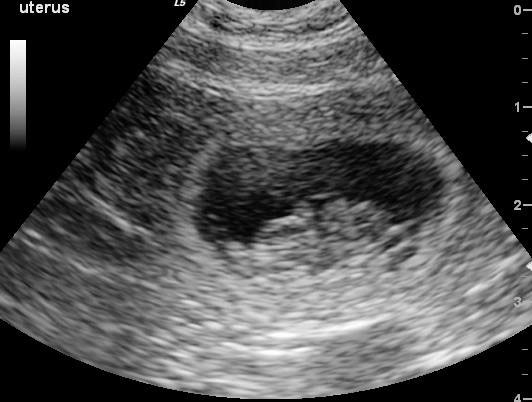

Pet Ultrasound

A non-invasive way to diagnose sick & injured pets.